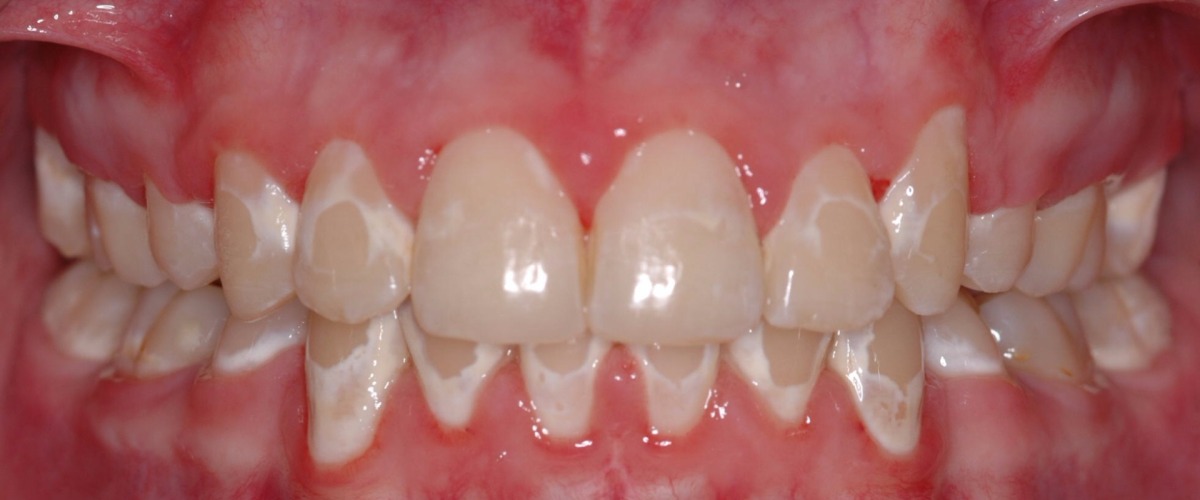

浅龋

破坏牙釉质,牙齿表面发黑有孔,一般没有明显的蛀牙洞,没有疼痛感。

治疗方法:树脂充填(补牙);采用正确的刷牙方式,养成良好的口腔卫生习惯,可以控制龋病发展。

牙齿脱矿